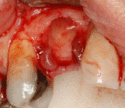

- Soft tissue reflection: An incision is made over the crest of bone, splitting the thicker attached gingiva roughly in half so that the final implant will have a thick band of tissue around it. The edges of tissue, each referred to as a flap are pushed back to expose the bone. Flapless surgery is an alternate technique, where a small punch of tissue (the diameter of the implant) is removed for implant placement rather than raising flaps.

For an implant to osseointegrate, it needs to be surrounded by a healthy quantity of bone. In order for it to survive long-term, it needs to have a thick healthy soft tissue (gingiva) envelope around it. It is common for either the bone or soft tissue to be so deficient that the surgeon needs to reconstruct it either before or during implant placement.[18](p1084)

Hard tissue (bone) reconstruction

To achieve an adequate width and height of bone, various bone grafting techniques have been developed. The most frequently used is called guided bone graft augmentation where a defect is filled with either natural (harvested or autograft) bone or allograft (donor bone or synthetic bone substitute), covered with a semi-permeable membrane and allowed to heal. During the healing phase, natural bone replaces the graft forming a new bony base for the implant.[23]:223